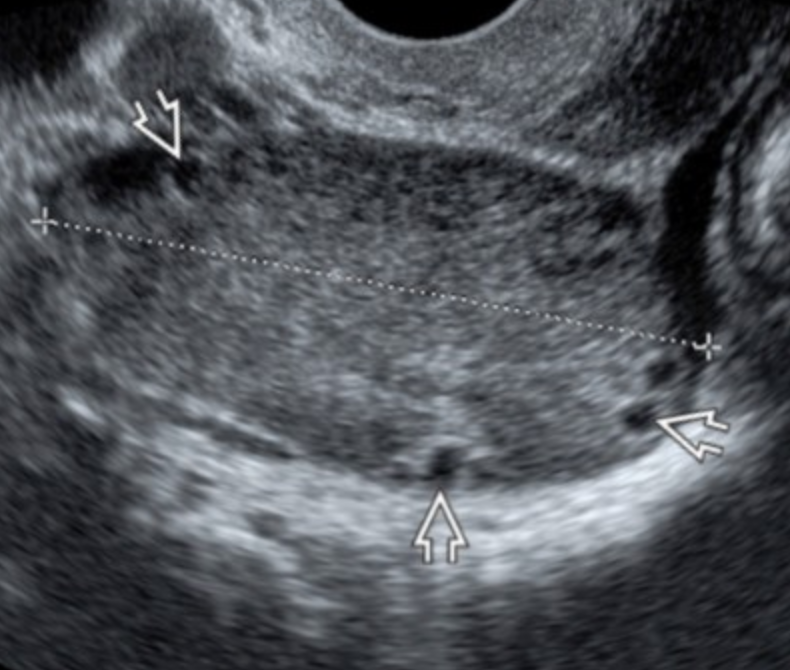

Hemorrhagic Cyst

• On US

• Fluid-fluid level

• High echogenic substance is in dependent portion and fluid is on top

• Fibrin threads

• Linear increased echogenic lines

• Has a cobweb appearance - US below

• Retractable clot (left thick arrow in US below)

• No color on doppler